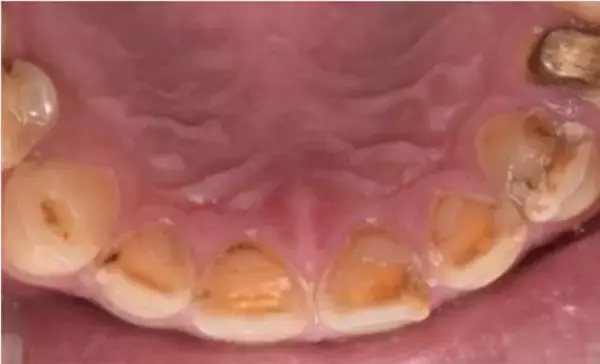

酸蝕歯で全体的に歯が溶けて、むし歯もみられる